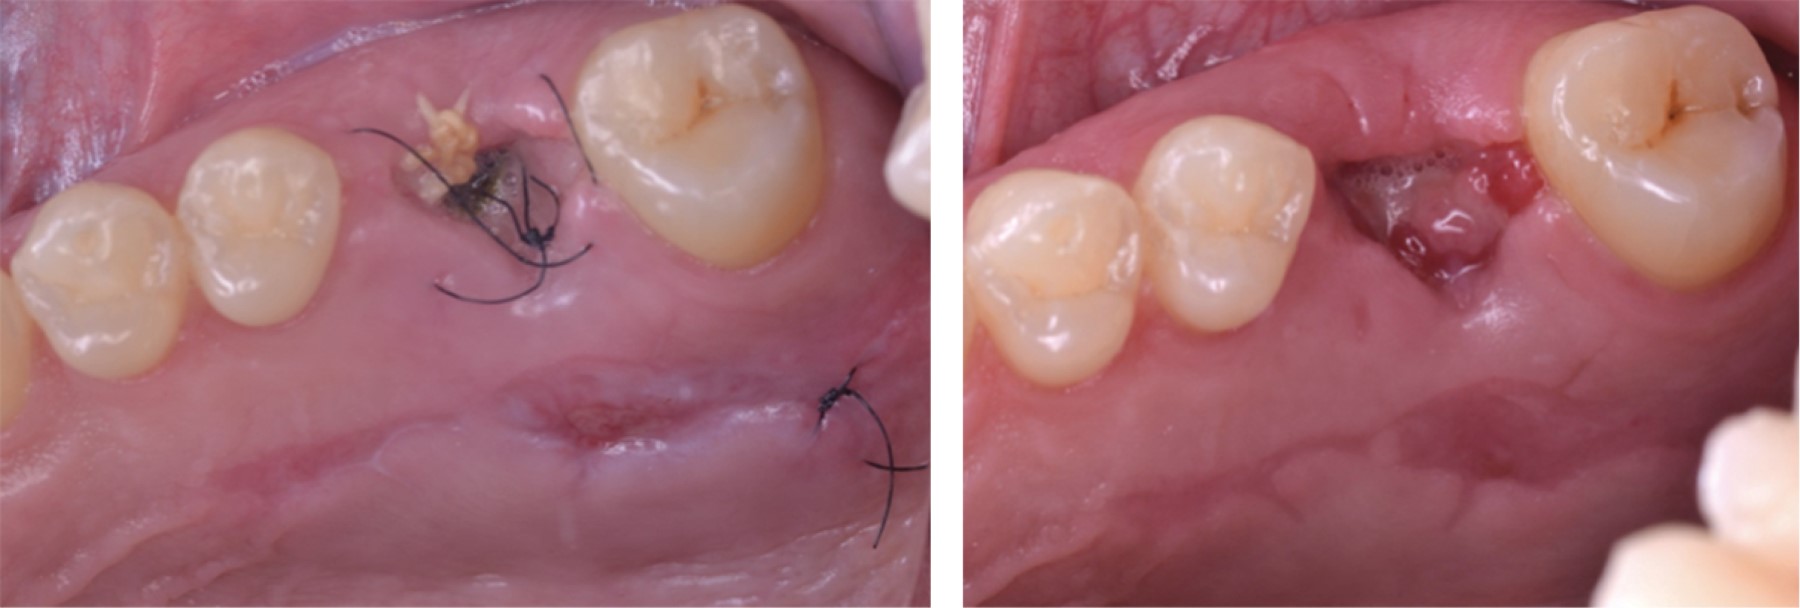

A la exploración clínica, se observó el primer molar superior derecho (OD #16) con aparente reconstrucción protésica, tejido dental remanente deficiente y una recesión palatina de en promedio cuatro milímetros y un sondaje en el sitio palatino de dos milímetros; lo que resulta en una pérdida de nivel de inserción clínica (CAL) de seis milímetros (Figura 1).

Se citó al paciente a 10 días de la intervención (Figura 7). Se observó el tejido palatino y del alveolo en proceso de epitelización con ligeras zonas de granulación. Se retiraron suturas de nilón y se citó al paciente dentro de cuatro días posteriores.

A los 14 días, se observó zona palatina aún en proceso de epitelización. En la zona del reborde, se observaron zonas ligeramente edematosas y eritematosas (Figura 7). Al mes se observó tonalidad de tejidos más uniforme, aunque todavía levemente eritematosa. A la fecha se observan resultados exitosos de la intervención, con base en la consistencia y tonalidad de los tejidos. A los seis meses se observa tonalidad de tejidos uniforme y una invaginación en la zona del alveolo. Se encuentra por completo epitelizada la zona de la recesión gingival (Figura 8).

Figura 1

Figura 6

Figura 7